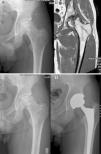

During the first 2 years after the intervention, hip arthroplasty was indicated in 5 (24.7%) of the 22 hips, after a mean period of 17.2 months following the infusion of BM concentrate. The baseline Arlet–Ficat stage in these cases was stage I in 1 case, stage II in 2 cases and stage III in the remaining 2 cases. A total of 3 arthroplasties were conducted on the 16 hips in stages I and II (18.75%) (Fig. 1) and 2 on the 6 hips in stage III (33.3%) (P=.9256). Out of the 17 hips which did not require arthroplasty, the VAS evaluation improved from a baseline value of 5.61 (±1.65) to 4.09 (±2.16); 4.66 (±2.26); 4.55 (±2.81) and 4.64 (±2.81) at 1, 6, 12 and 24 months, respectively. The mean decrease in VAS at 24 months compared to the baseline value was 0.98 points (P=.089).